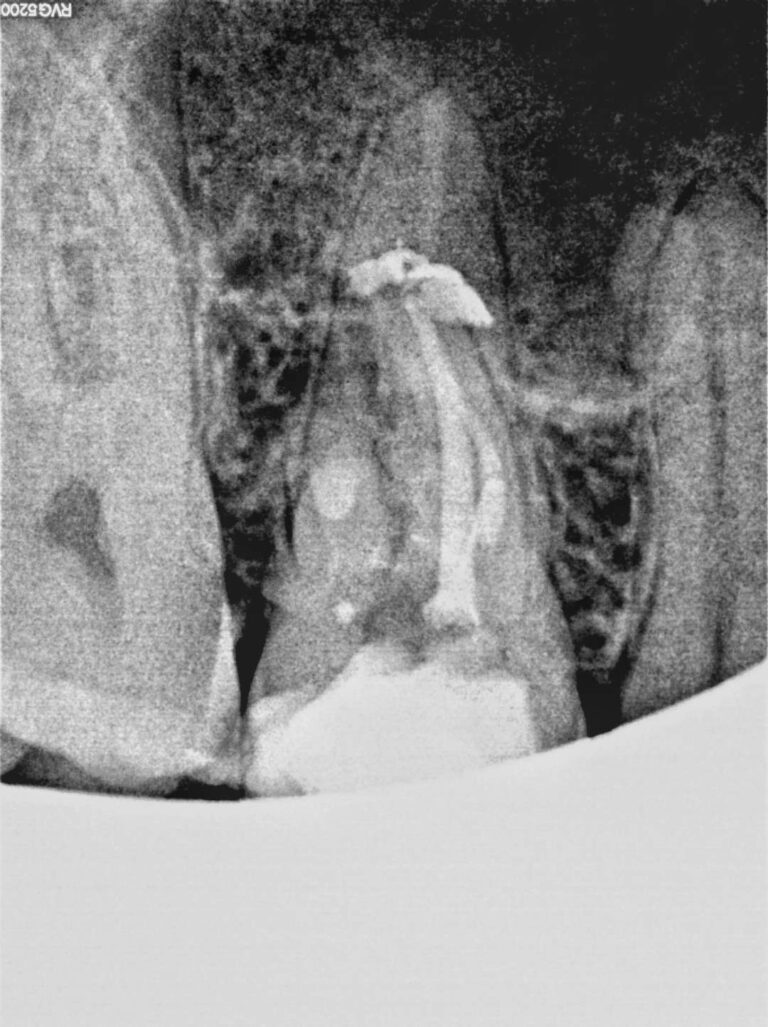

Cirurgia apical para remoção de quisto